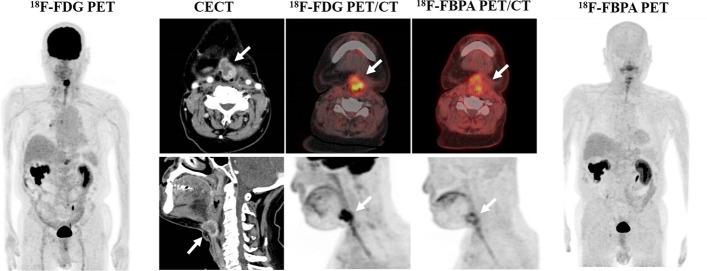

The goal of the study was to evaluate the diagnostic ability of F-FBPA PET/CT for malignant tumors. Findings from F-FBPA and F-FDG PET/CT were compared with pathological diagnoses in patients with malignant tumors or benign lesions.

A total of 82 patients (45 males, 37 females; median age, 63 years; age range, 20-89 years) with various types of malignant tumors or benign lesions, such as inflammation and granulomas, were examined by F-FDG and F-FBPA PET/CT. Tumor uptake of FDG or FBPA was quantified using the maximum standardized uptake value (SUVmax). The final diagnosis was confirmed by cytopathology or histopathological findings of the specimen after biopsy or surgery. A ROC curve was constructed from the SUVmax values of each PET image, and the area under the curve (AUC) and cutoff values were calculated.

The SUVmax for F-FDG PET/CT did not differ significantly for malignant tumors and benign lesions (10.9 ± 6.3 vs. 9.1 ± 2.7 P = 0.62), whereas SUVmax for F-FBPA PET/CT was significantly higher for malignant tumors (5.1 ± 3.0 vs. 2.9 ± 0.6, P < 0.001). The best SUVmax cutoffs for distinguishing malignant tumors from benign lesions were 11.16 for F-FDG PET/CT (sensitivity 0.909, specificity 0.390) and 3.24 for F-FBPA PET/CT (sensitivity 0.818, specificity 0.753). ROC analysis showed significantly different AUC values for F-FDG and F-FBPA PET/CT (0.547 vs. 0.834, p < 0.001).

F-FBPA PET/CT showed superior diagnostic ability over F-FDG PET/CT in differential diagnosis of malignant tumors and benign lesions. The results of this study suggest that F-FBPA PET/CT diagnosis may reduce false-positive F-FDG PET/CT diagnoses.